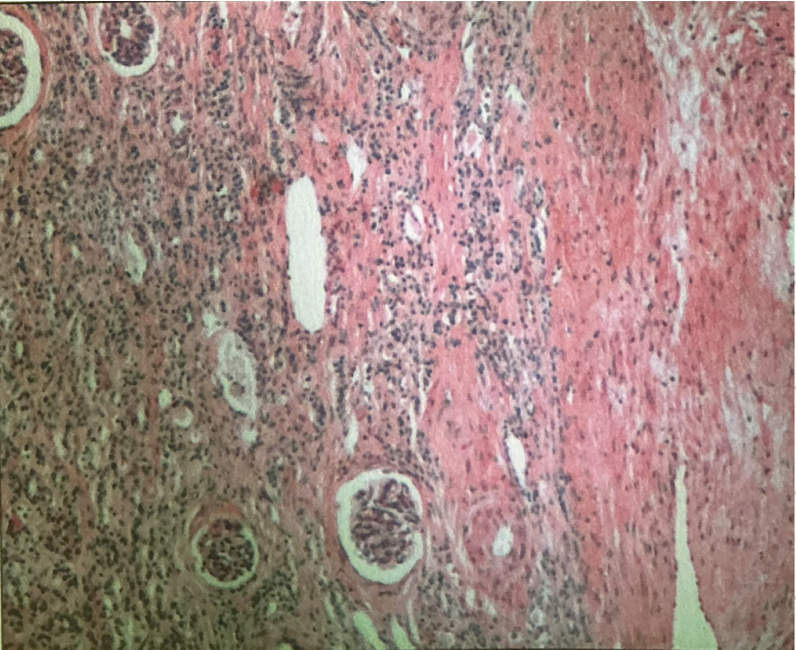

hodgkin’s granuloma

hodgkin’s granuloma

cancer of lymph system - breakdown of red and white pulp

reed-sternberg cells

derived from B lymphocytes